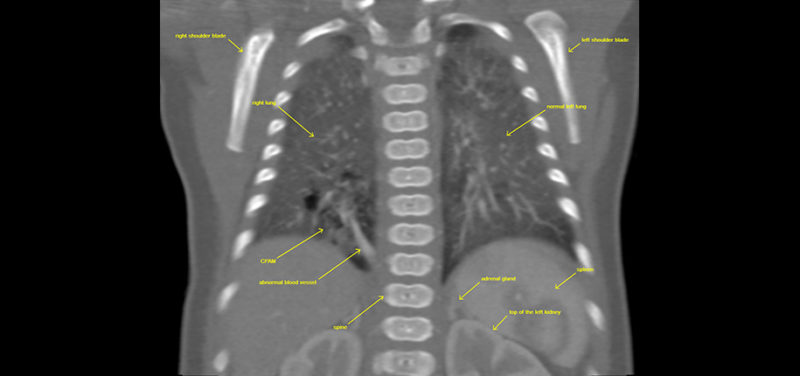

For example, one of our cardiothoracic radiologists, a doctor who looks at images of the heart, lungs and airway, is working with one of our fellows to see if there is a better way to look at infants with a lung abnormality known as CPAM (congenital pulmonary airway malformation). A CPAM is an abnormality of lung development that can make it difficult for a baby to breathe when he or she is born. A CPAM can also rarely lead to cancer if it is not removed. As a result, surgery is usually necessary to remove the CPAM.

Before surgery, a CT scan is often requested to see the size and location of the CPAM and to see if there are any abnormal blood vessels flowing into or out of the CPAM. This CT scan provides important information to the surgeon, which allows for faster operations with fewer complications.

Traditionally, the CT scan done to look at the CPAM is designed to focus on the blood vessels using a technique called CTA (CT angiography). Our research team found that using a standard CT technique was able to answer the surgeon’s questions just as well as the CTA technique and at HALF the radiation dose! See if you notice any difference between the image obtained with the traditional CTA technique and the image obtained with the standard CT technique, as shown below.

Image: CT coronal image right lower lobe CPAM with abnormal blood vessel.

Image: CT coronal image right lower lobe CPAM with abnormal blood vessel.

Image: CTA coronal image left lower lobe CPAM with abnormal vessel.

Image: CTA coronal image left lower lobe CPAM with abnormal vessel.